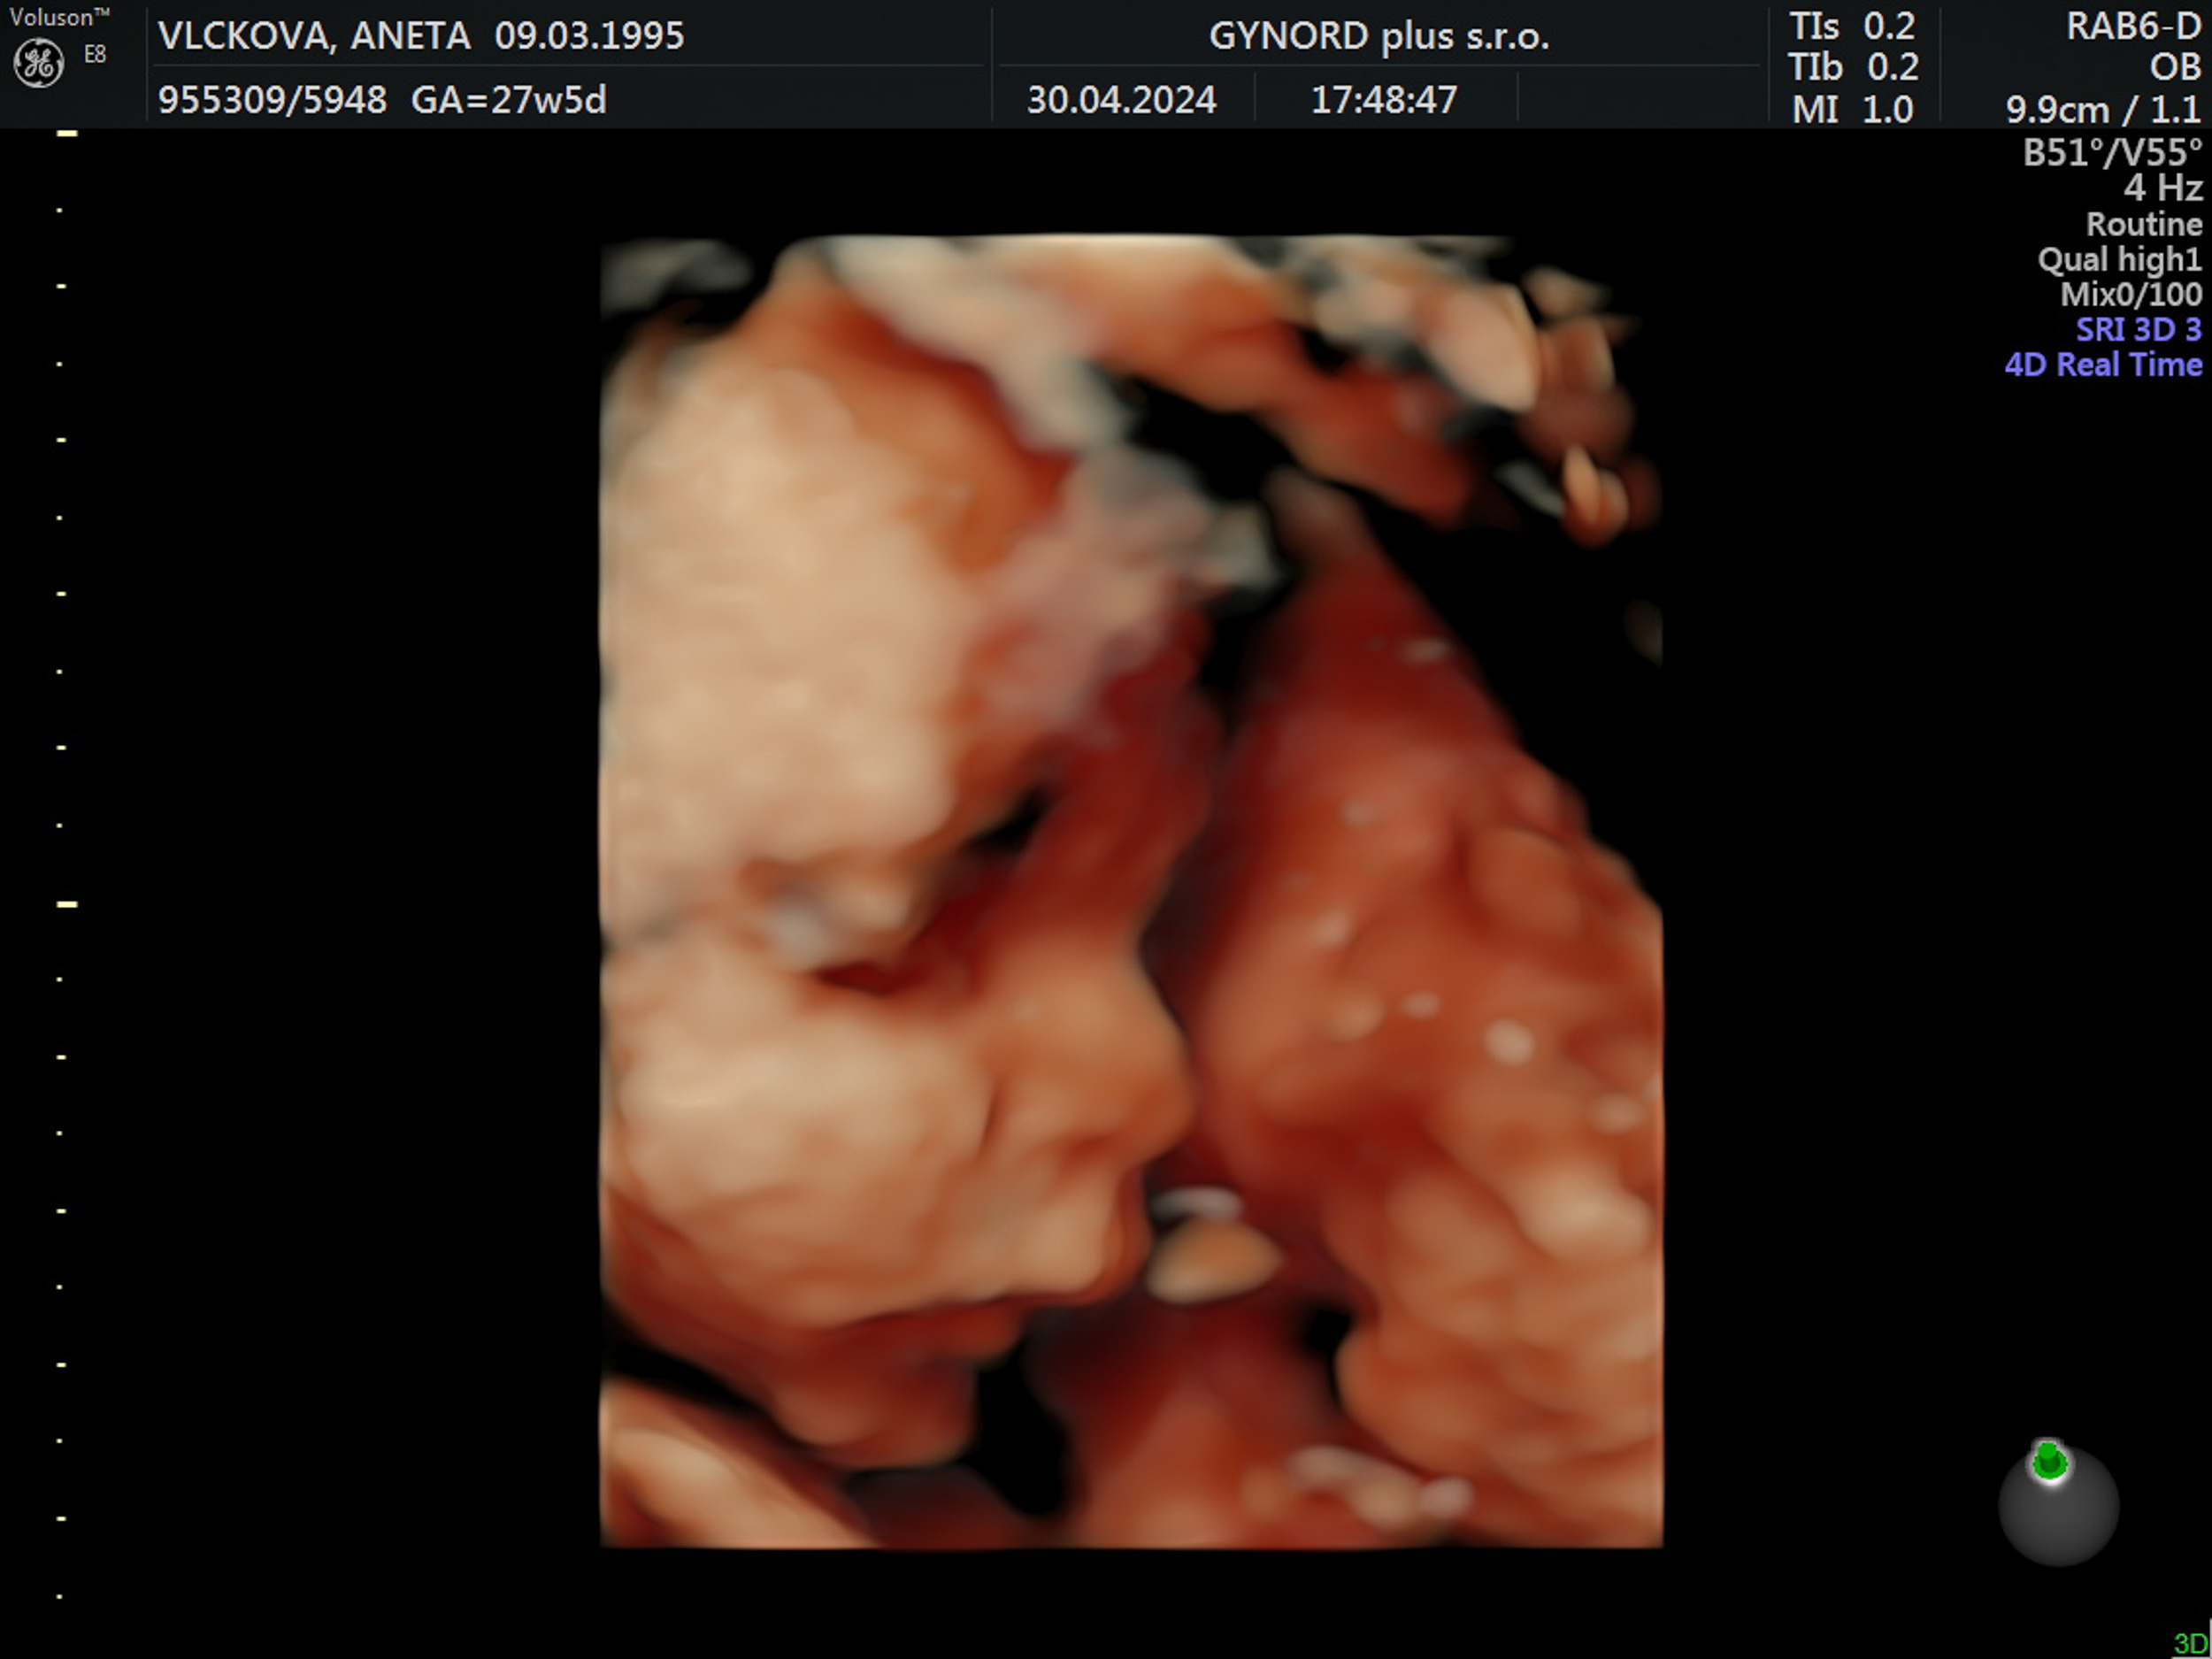

Tomášek - ještě v bříšku